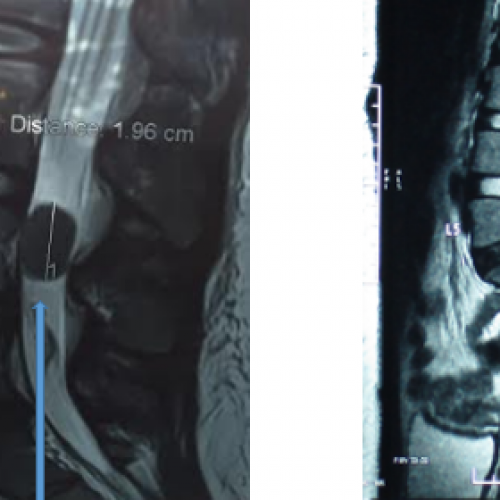

脊髓( spinal cord )是神經系統中重要的一部分。在顱頸的交會處,脊髓向上承接腦幹後,便被嚴密的保護在脊椎的神經腔中,由頸部一直延申到腰椎;右圖即是脊髓在脊椎內分佈情形。

脊髓的外側有一層硬膜( dura )包覆,硬膜之內充滿了腦脊髓液。脊髓本身即有一層軟膜包著。